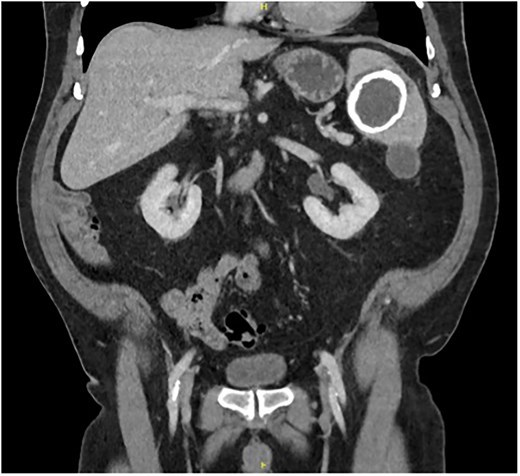

A 67-year-old gentleman was referred for management of a symptomatic, large splenic cystic lesion that had been found incidentally on coronary angiography in 2012. He had been worked up by his general practitioner at the time with a computed tomography (CT) scan which demonstrated a large, well-defined calcified splenic cyst measuring 8 cm in size (Fig. 1) and negative hydatid serology. On serial imaging over the following decade, the lesion was found to be mostly stable in size and was therefore only referred to a surgeon for definitive management in 2024 due to new symptoms of left upper quadrant (LUQ) abdominal pain and refractory nausea. This was accompanied by early satiety and unintentional weight loss of 10 kg over the preceding year. He had a medical history significant for coronary artery disease, dyslipidaemia, benign prostatic hyperplasia, and chronic obstructive pulmonary disease, and a surgical history significant for open epigastric, umbilical, and bilateral inguinal hernia repairs.

Coronal portal venous phase CT scan of the abdomen and pelvis demonstrating the calcified splenic lesion.